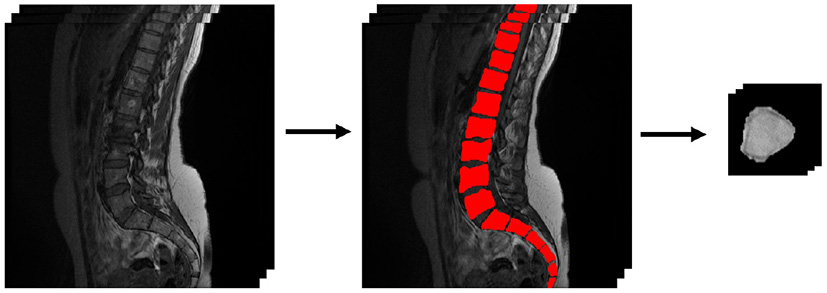

The individual vertebrae in this work were manually 2D segmented and extracted from the rest of the spine (ref. Figure 1). Each of these images was limited to a size of 64 × 64 pixels. Vertebral bones that could not be seen well or are no longer complete at the upper edge of the image are not used for training the AC-GAN. As a result, the dataset in this work includes 693 MRI slice images. All vertebral bodies that were fully depicted on each slice were classified by an experienced radiologist (KZ: 7 years experience in clinical musculoskeletal imaging and research). As a result, 540 vertebral bodies were classified as healthy, 47 of them were classified as abnormal but not pathological (e.g., hemangioma, benign sclerotic lesion, focal fat metaplasia, intraspongious disc herniation) and 106 vertebral bodies were classified as pathological (fracture, spondylitis, metastasis). For training the classification network, these 693 slice images are augmented with the excluded image data (total 716 images). In addition, 200 generated images from each class are added to the dataset.

Figure 1

Segmentation and extraction of the data basis.